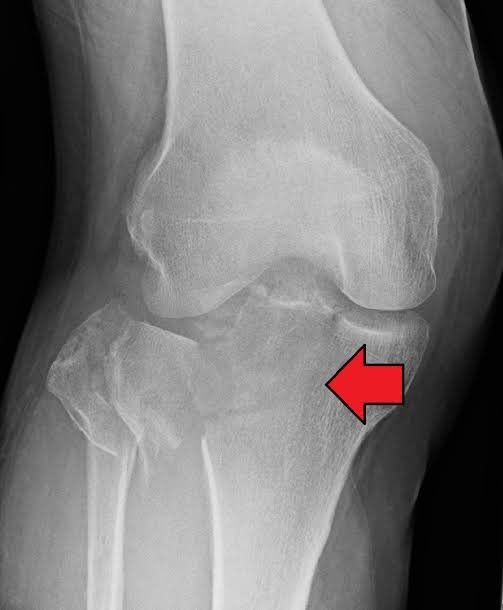

2. Cedera Lutut yang tidak ditangani dengan baik

Nah ini jg byk kasusnya, kasus2 patah tulang di dekat sendi,jka tdk ditangani dgn baik AKAN SANGAT MEMPERCEPAT proses OA,bahkan bisa terjadi di usia 20an lho.

Karena posisi tulang sendi yg baik adalah sarat utama sendi kita sehat

Selain cedera tulang, cedera struktur lain di lutut jg dipercaya akan mempercepat proses osteoarthritis

Misalnya cedera meniscus/bantalan sendi lutut, bisa jg pada kasus cedera ligamen..

JIKA TIDAK DITANGANI DENGAN BAIK .

Jadi segera berobat ke dokter ya gaes kalo ad cedera

Nah utk kasus cedera ligamen/meniskus ini banyak ni di temen2 yg sering main sepakbola/voli/basket

Gejalanya mulai dari nyeri,lutut goyang, susah lari/bertanding lagi, bahkan pada kasus tertentu sampe kaku dan ngunci, bisa jg bengkak dan sering sakitt

Segera berobat ya